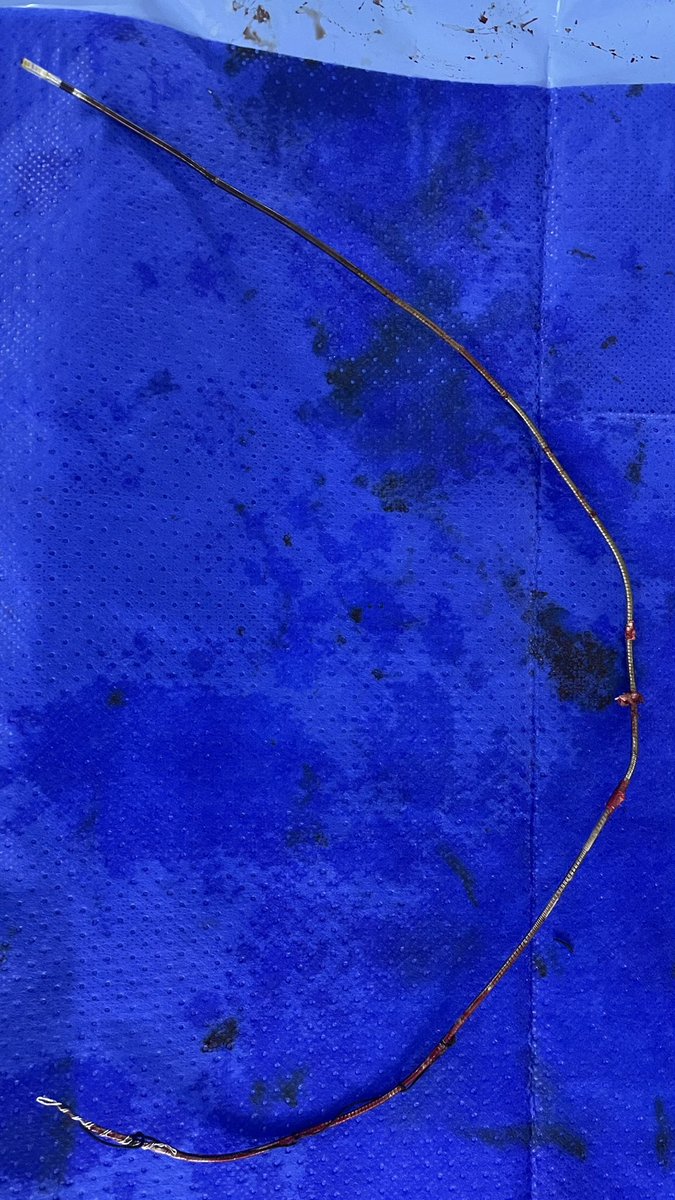

Another successful extraction. This was a challenging one for an early career, “flying solo” extractor. High risk extraction, Morbid obese, with 11 yo CRT-D, dual coil, pace dependent. Coming with sepsis, positive BC and lead vegetations. Thanks @HNayakEP @ABeaser for the wisdom

0

1

11